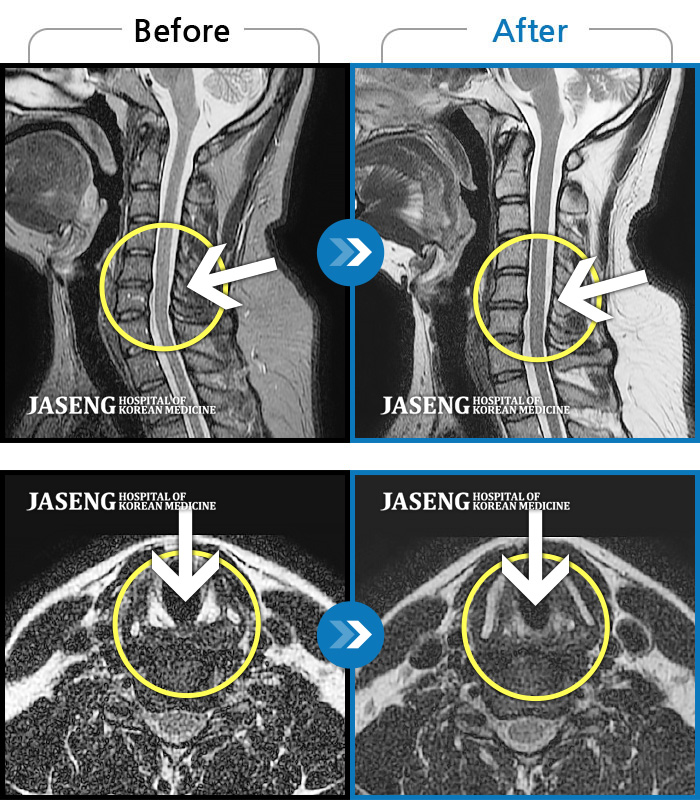

목디스크

도움받은 사례

인천 · 강아현 원장

처음 내원시 목에서 등으로 이어지는 통증 및 우측 팔 저림 증상이 심했고, 약간의 근력저하도 동반되어 일상생활이 어려운 상태였습니다.

촬영시기

2024.04.06 ~ 2024.11.16

2024.11.22

조회수 17,045